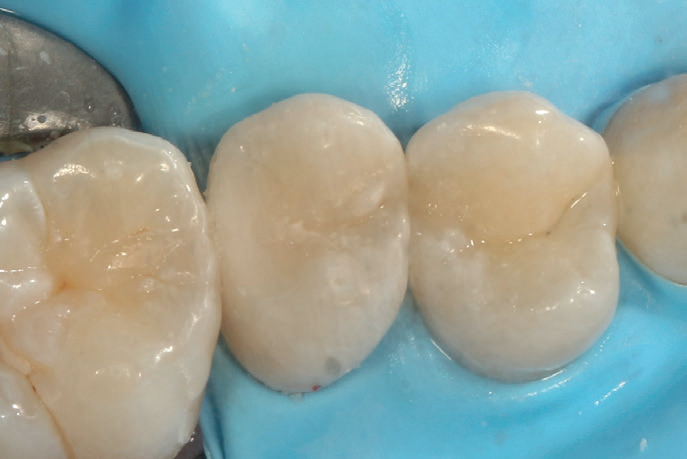

After placing the filling, I let the material set for a few minutes, then carried out final trimming and polishing without additional curing lights, simplifying the procedure even further.

Figure 10: Postoperative images after occlusal adjustment. Two fillings placed UR4 and UR5

The restoration remained intact with no complications

The material’s natural translucency allowed it to blend seamlessly with the surrounding tooth structure, a crucial factor due to the cavity’s location. Furthermore, Stela’s superior mechanical properties, including high flexural and compressive strength, made it an ideal choice for a restoration designed to withstand everyday function.